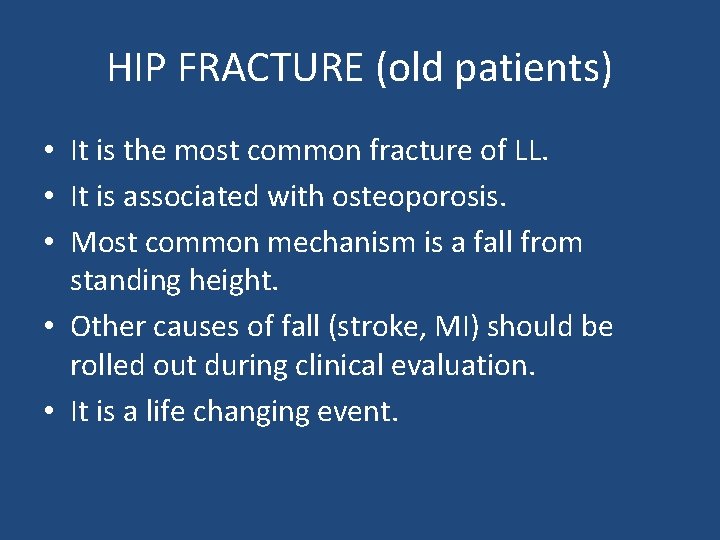

HIP FRACTURE (old patients) • It is the most common fracture of LL. • It is associated with osteoporosis. • Most common mechanism is a fall from standing height. • Other causes of fall (stroke, MI) should be rolled out during clinical evaluation. • It is a life changing event.